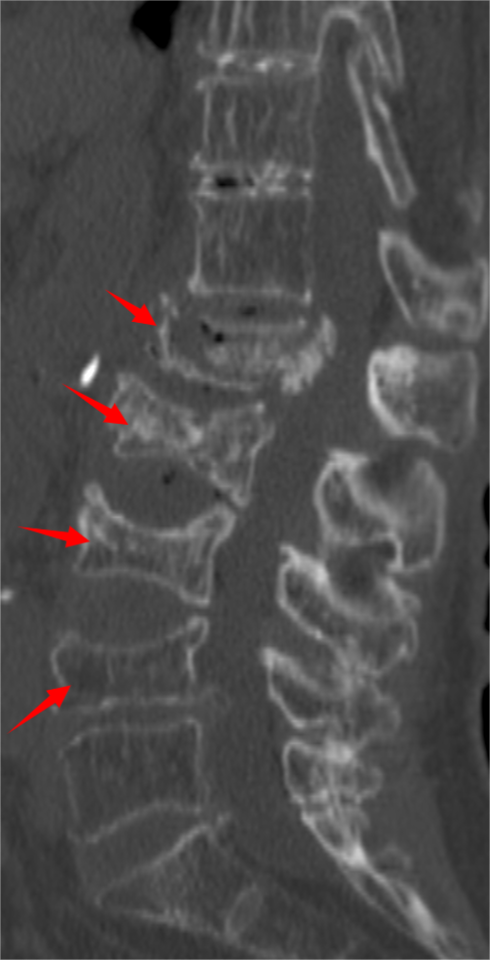

胸腰椎MRI检查结果显示:腰1椎体新近压缩性骨折伴积气,继发椎管狭窄;腰2、3椎体及腰4椎体上缘新近骨折。

影像学结果明确了患者为“骨质疏松伴多节段病理性骨折”,并伴有明显的脊柱后凸畸形和腰椎不稳。骨密度检测T值-4.25,提示重度骨质疏松。

影像学检查提示多节段脊柱病变

接诊后,科室为吴婆婆安排了详细的影像学检查,结果令人震惊。磁共振显示,她的骨折远非此前所知的一处,骨折下方的三节椎体腰2至腰4多个椎体都出现了新鲜压缩性骨折。更关键的是,最初的腰1椎体骨折并未愈合,属于“骨折不愈合”状态,并在重力作用下逐渐塌陷,导致脊柱后凸畸形(俗称“驼背”)。